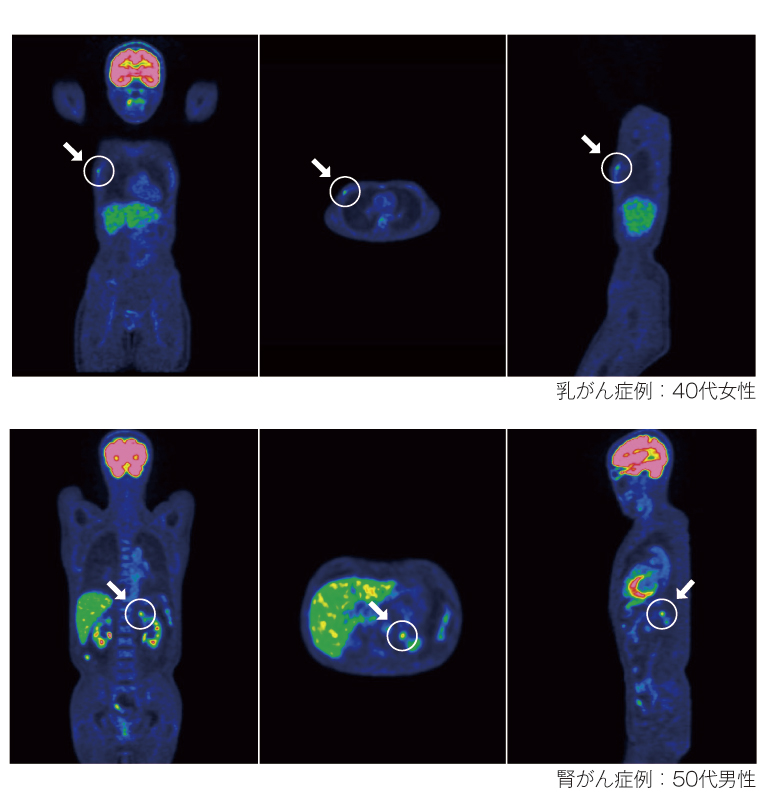

がん細胞は正常の細胞よりも分裂が盛んに行われるため、エネルギー源としてブドウ糖をたくさん必要とします。そこで、ブドウ糖に似た性質の物質に、微量の放射線を放出する放射性同位元素を標識したくすり(FDG)を静脈から投与すると、正常細胞よりもがん細胞にたくさん集まります。PET装置でこのFDGの集まる様子を撮影し、がんの位置や大きさを画像で表します。

右図:がん細胞は正常な細胞よりも多くの糖を必要とするため、たくさんのFDGが集まります。

FDGの集まり具合は、白黒画像では濃淡で、カラー画像では色の違いとして表示されます。活発に活動をする脳の神経細胞や心筋などにはFDGの生理的な集積が認められます。FDGは尿として排出されるため、腎臓や尿管、膀胱にも集積します。また、炎症細胞や良性腫瘍にも集積します。FDGが集まっている場所すべてが、がんではありません。

通常頭部から骨盤までの広い範囲を一度に撮影します。原発巣の探索や、転移の有無の診断に有用です。通常の検診では検査対象とならない思いがけない場所に、がんが発見されることもあります。

画像提供:浜松PET診断センター